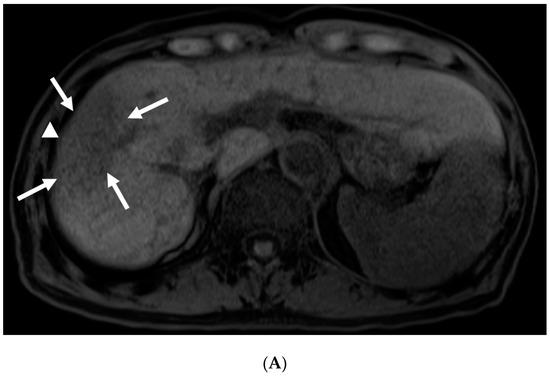

3.2. Imaging Follow-Up

3.4. Pathological Findings and Estimated Theory of FLR Mechanisms